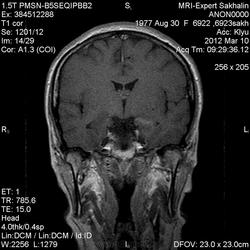

Провели дополнительное контрастирование:

Лимбический энцефалит? Паранеопластический процесс? А где диффузионные программы- не помешают. Нужно подумать (или спросить у ннемо, например))).

Написала дифф.ряд: лимбический энцефалит, лимфому ЦНС, герпетический энцефалит.

С лимфомой верифицированной не встречался, картина не противоречит паранеопластическому или герпетическому энцефалиту. Склероз гиппокампов: нет уменьшения их размеров, зоны изменений сигналов гиппокампами не ограничиваются, есть кроме височных долей и в ножках мозга, опять же накопление контраста.

Для И.Бондаренко - вы все правильно указали - гипер- в Т2W, а также гипо- в Т1W, + очаги накопления контраста

Есть и давно подтвержденное понятие паранеопластический лимбический энцефалит - как вариант примерно так и будет выглядеть.

(не хватает данных DWI и желательно при таких делать fatsat добавлять при контрасте как то лучше накопление по оболочкам видно, также не помешало бы и Т1mgt ну или двойную/тройную дозу контраста)

В данном случае больше данных за воспалительный энцефалит - есть синусит (не нравиться гиперинтенсивное включение парацентрально в пазухе -грибок????) .

С учетом накопления контраста да и по локализации однозначно не опухоль, не инсульт, не травма. Из классики да действительно герпес любит виски, также и иные вирусные могут быть (этиологию иной раз не угадаешь - бессмыслено), может быть и тбс. но сос четов не сбрасывал бы паранеопластический - тем более женщина да и контраст накопила как бы не молочка?? Ну и совсем чтоб запутать нет ли В20? только на внешний вид и на мужа не надо ориентироваться - у нас и у врачей и у студентов мед вузов бывает - пройденный этап(((

Была у нас пациентка (картинки предоставить не могу , так как поезд ушел) , картина была один в один , только в меньшей степени выраженности. Тоже возникло после перенесенной ОРВИ, после лечения приходила на контроль - мр- сигнал вернулся к норме. Так что согласна с энцефалитом. При паранеопластическом процессе все же более четкие границы , я так думаю. и распостраненность несколько другая..